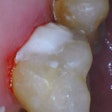

A large onlay: "When used as an onlay, the gold can protect cusps from future fractures better than any other material," said Karl-Johan Söderholm, D.D.S., Ph.D., a professor of materials science and engineering at the University of Florida.

A dark stump: Gold can cover the color better than lighter materials.

Heavy wear: "During wear, gold will retain a smooth surface, while tooth-colored restorative materials such as ceramics tend to become rough and accelerate wear of opposing teeth," Dr. Söderholm said. Gold can also withstand a grain of sand that might fracture ceramic.

Adjustments needed in the dental office: Because of its malleability, you can bend, burnish, and trim gold to exactly fit the margin.

Opposing an existing gold restoration: Porcelain or other harder materials could damage the gold when the patient bites down or grinds teeth.